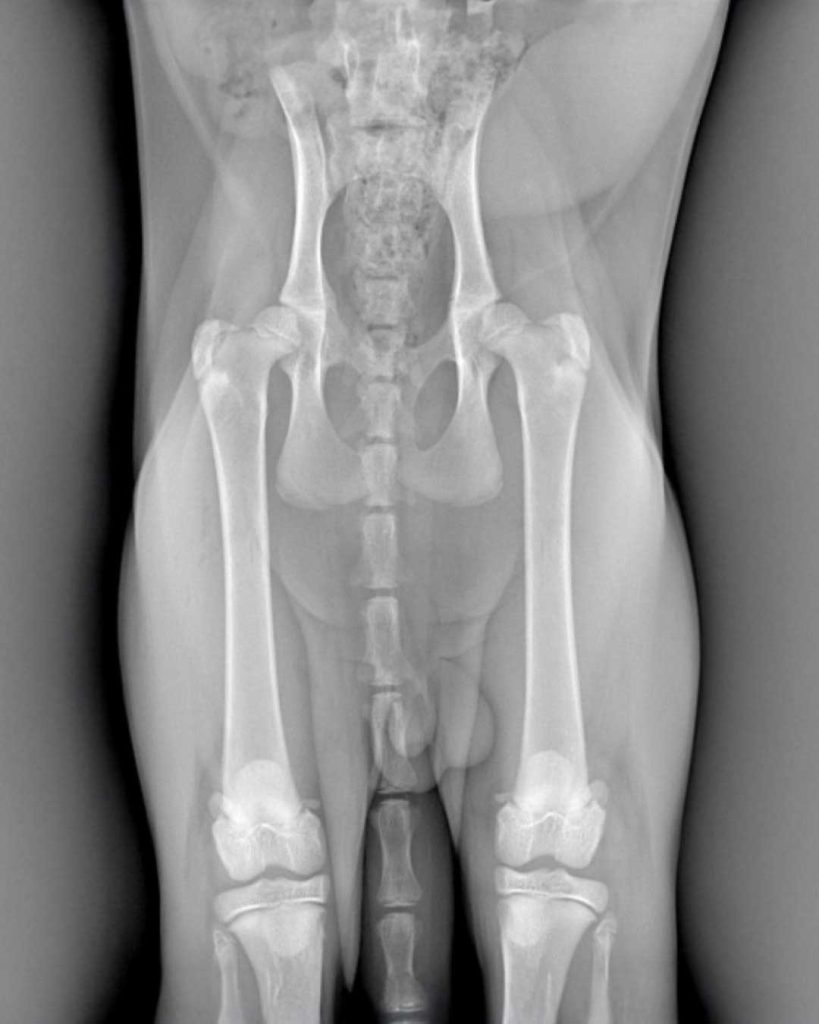

- protesi totale d’anca (THR)

In questi casi la precisione chirurgica è tutto: ogni grado di inclinazione o millimetro di allineamento influisce direttamente sulla funzionalità del movimento, sulla durata dell’impianto e sul benessere a lungo termine del paziente.